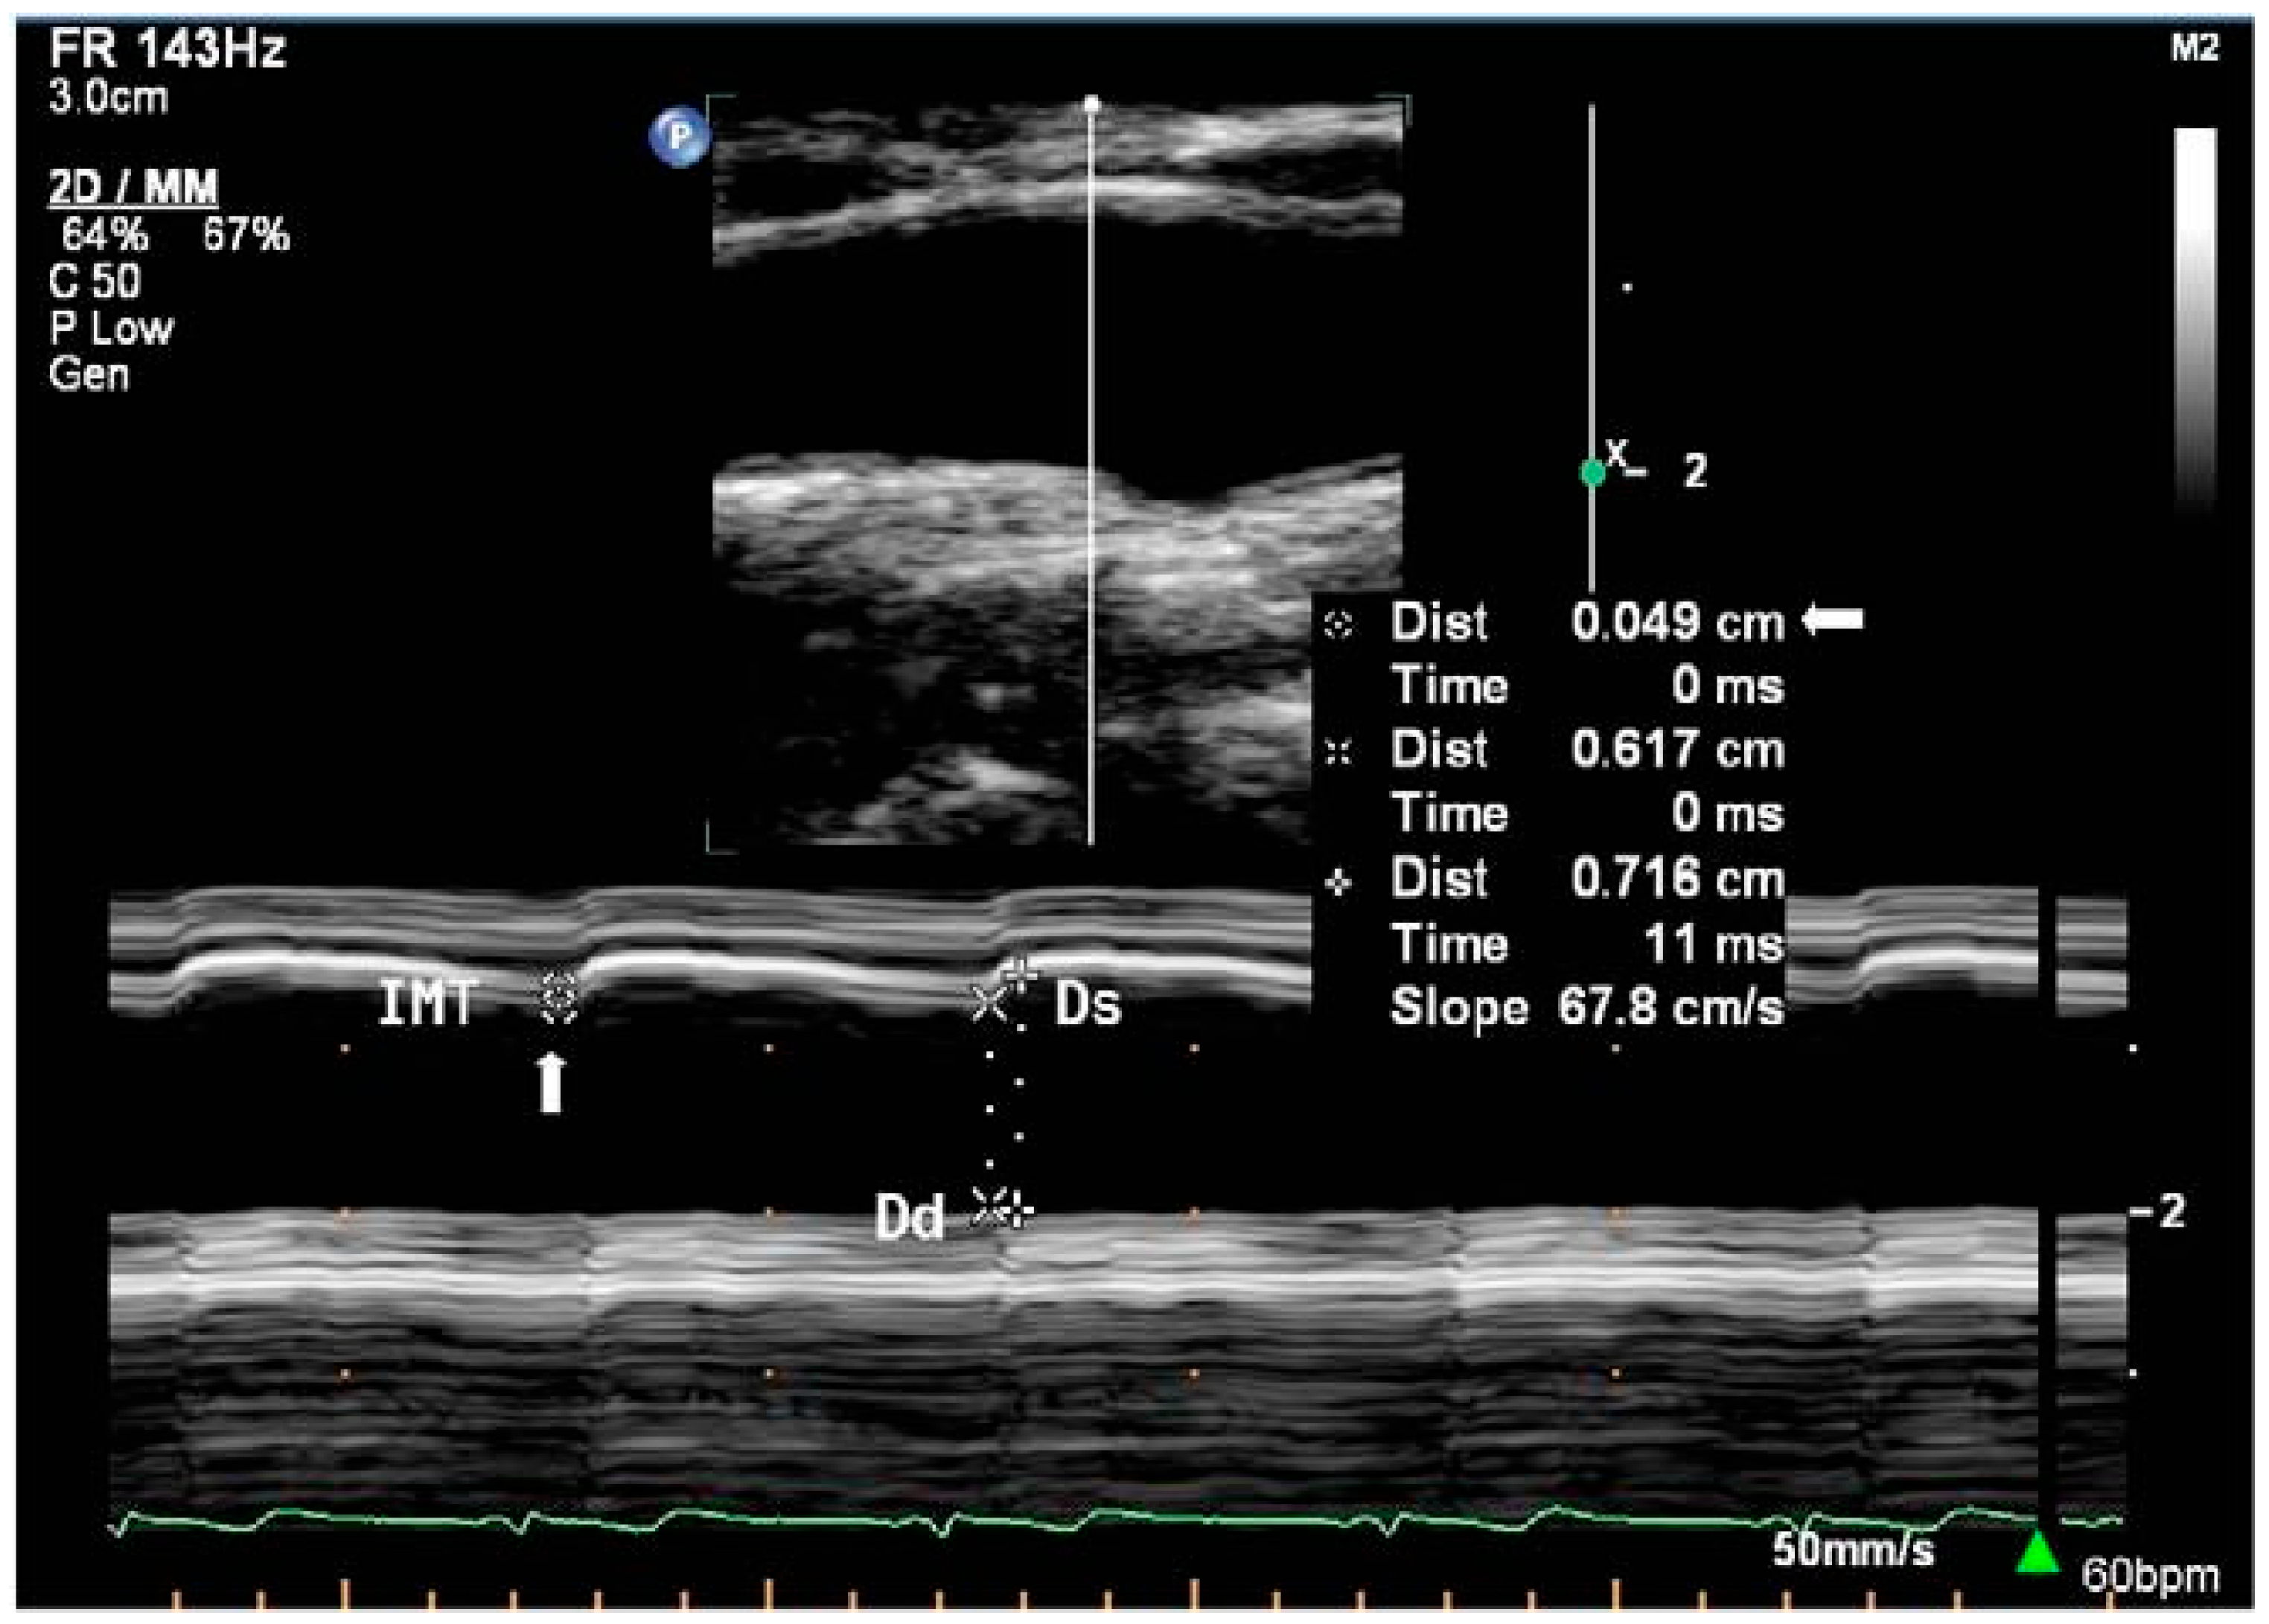

In area or diameter measurement, sound waves emitted by the transducer are partially reflected and transmitted at tissue boundaries with different acoustic impedances in the beam path, which causes differences in the echo return time and facilitates detection of different tissues at different depths [38]. There are three main imaging modes available on ultrasound machines, namely Amplitude (A-mode), Brightness (B-mode), and Motion (M-mode). A-mode ultrasound provides a one-dimensional scan line that displays the strength of the echoes as vertical peaks on a graph. While some studies have explored the use of A-mode ultrasound in simple system configurations to measure diameter [107,108,109], its use remains relatively under-represented in the literature relating to diameter and area acquisition. Hence, only B-mode and M-mode (Figure 2) ultrasound will be discussed. The functioning principles and use of each modality in measurement are summarised in Table 1.

• M-mode imaging displays the displacement of a detected tissue boundary graphically (Figure 3) for diameter measurement

An early non-simultaneous acquisition method utilised in [31] employs B-mode imaging for diameter acquisition and PW Doppler imaging for velocity acquisition before using the lnDU loop for PWV estimation. This method involves obtaining B-mode images with the region of interest in the focal zone, where images should clearly capture anterior and posterior walls, to reduce noise and obtain optimal diameter curve measurement. Subsequently, using the same scan projection, PW Doppler measurement is conducted with as small an angle correction as possible to prevent shifts in the scan location [31]. In this method, angle correction is needed, as Doppler imaging requires the Doppler angle for frequency shifts and velocity measurement. Studies employing this methodology typically use high-frame-rate electrocardiogram (ECG) gating to prevent a mismatch in features of both diameter and velocity curves over each cardiac cycle by allowing for time alignment, which uses the ECG to set a trigger signal [151,152].

In contrast, Rabben et al. [19] proposed a different non-simultaneous acquisition method that utilises M-mode imaging instead of B-mode imaging to record ultrasound data over three to five cardiac cycles for diameter acquisition. Akin to the previous method, after diameter acquisition, PW Doppler imaging is used to extract maximum velocities across the vessel before using the QA loop for PWV measurement. To ensure proper alignment, the intima layers for both anterior and posterior walls should be clearly visible. According to [19], in this non-simultaneous acquisition method, the adjustment of the transducer allowed for optimal data collection, wherein the diameter distension measurements were of high accuracy and precision.